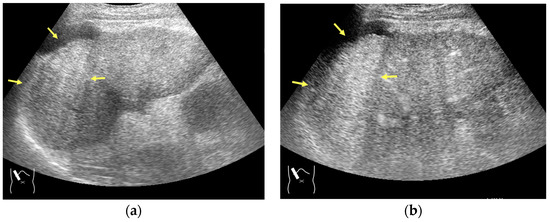

Next, we discuss the pulse inversion (PI) method and the amplitude modulation (AM) method, which are two representative modes that are frequently used in CEUS examinations [33]. Since there are some differences between the CEUS images obtained using these two methods, it is necessary to distinguish between them when performing CEUS examinations. As shown in Figure 2, the PI method is based on the sum of the first pulse and its inverted second pulse. If the tissue does not move between these two pulses and only the signal from a bubble remains unstable, then only the signal from the bubble is displayed with no background information (Figure 2a,b). In practice, however, the background signal is often not fully eliminated because of slight tissue movement. The AM method attempts to alleviate this problem of a “sooty” background. In the AM method, instead of two inverted pulses of the same magnitude (1-1), three pulses of the form 1/2-1+1/2 are emitted and summed to ensure the elimination of the signal from the background (Figure 2). Actual clinical images are presented. As shown in Figure 2, the AM method improves diagnostic accuracy by eliminating high-echo areas in the background. However, it also has the disadvantage that the image’s real-time nature is reduced as the number of US pulses increases. These two modes are available in most of the current high-end machines, but the current guidelines do not illustrate their proper use [34,35]. This increases flexibility for diagnosticians but also causes difficulties in choosing the right CEUS mode, resulting in randomness in mode selection. The basic strategy is to use one mode after another for comparison. However, the most simple and reliable method is to use the AM mode when the target lesion is highly echogenic (Figure 2c) and to otherwise use the PI mode. Nevertheless, individual adaptation should be determined each time to balance the optimal CEUS image quality, namely the maximal signal separation between the tissue and contrast medium and the optimal frame rate. However, the frame rate is crucial for accurately recording the beginning of the wash-in and wash-out. A frame rate of 10 frames/s or more is usually considered for liver tumor characterization [33].

Figure 2.

Amplitude modulation vs. the pulse inversion method: (a) Schematic drawing of pulse inversion (PI) mode. Substraction a − b = residual echo. (b) Schematic drawing of amplitude modulation (AM) mode. Substraction (a + c) − b = residual echo. (c) Gray-scale US shows a 4 × 4 cm heterogeneous mass (metastasis from colon cancer) (arrows) in the segment 6 (c). CEUS in amplitude modulation mode clearly demonstrates a punched out defect, leading to the diagnosis of liver metastasis (arrows) (d). CEUS in pulse inversion mode shows a heterogeneous detection (arrows) in a later phase (e).